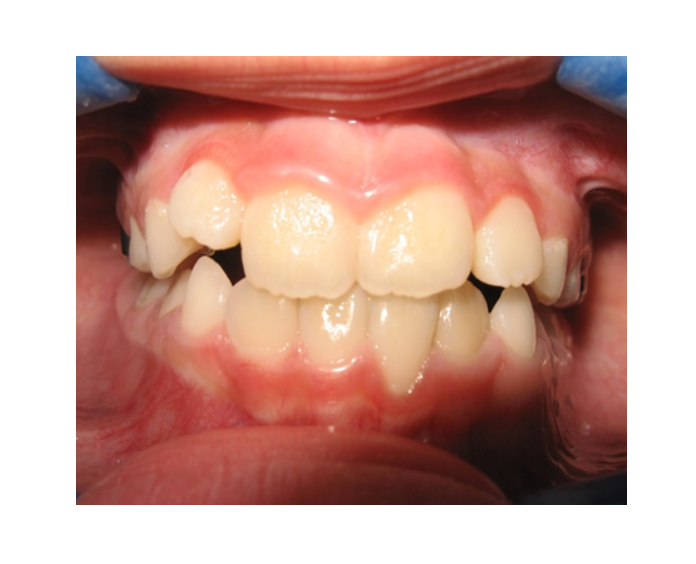

Mordida Cruzada posterior unilateral